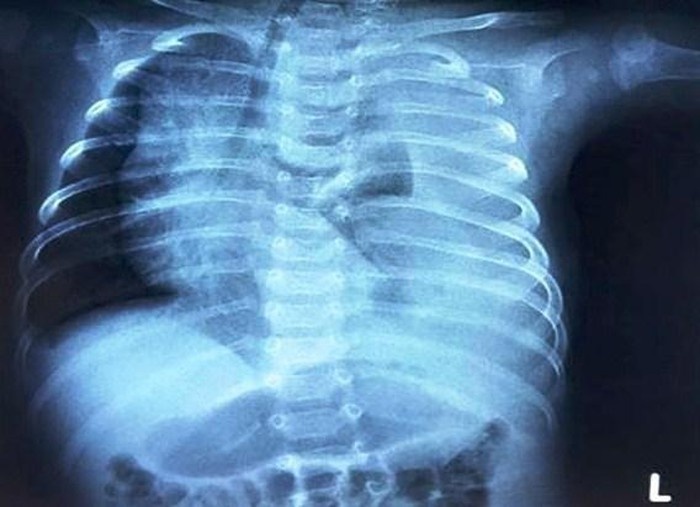

Bệnh viện Nhi đồng 2 TP.HCM cho biết em bé 3 tháng tuổi vừa nhập viện trong tình trạng khó thở. Bác sĩ phát hiện bệnh nhi bị rò dịch dưỡng trấp khoang màng phổi.